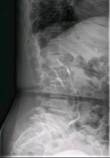

术前CTA检查